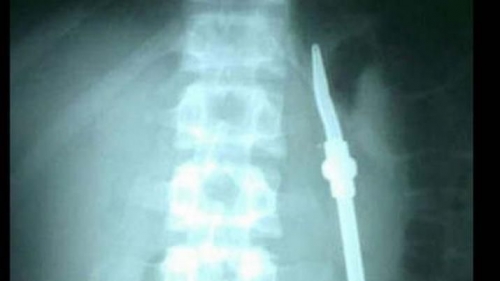

Ante la insólita situación y para evitar que la salud del joven pudiera sufrir algún contratiempo, el preso fue trasladado al Hospital Regional, en donde fue sometido a diversos estudios. Allí constataron los dichos por el sujeto, ya que las placas radiográficas mostraban la presencia de objetos extraños en el abdomen, por lo que en horas de la mañana de ayer fue intervenido quirúrgicamente.